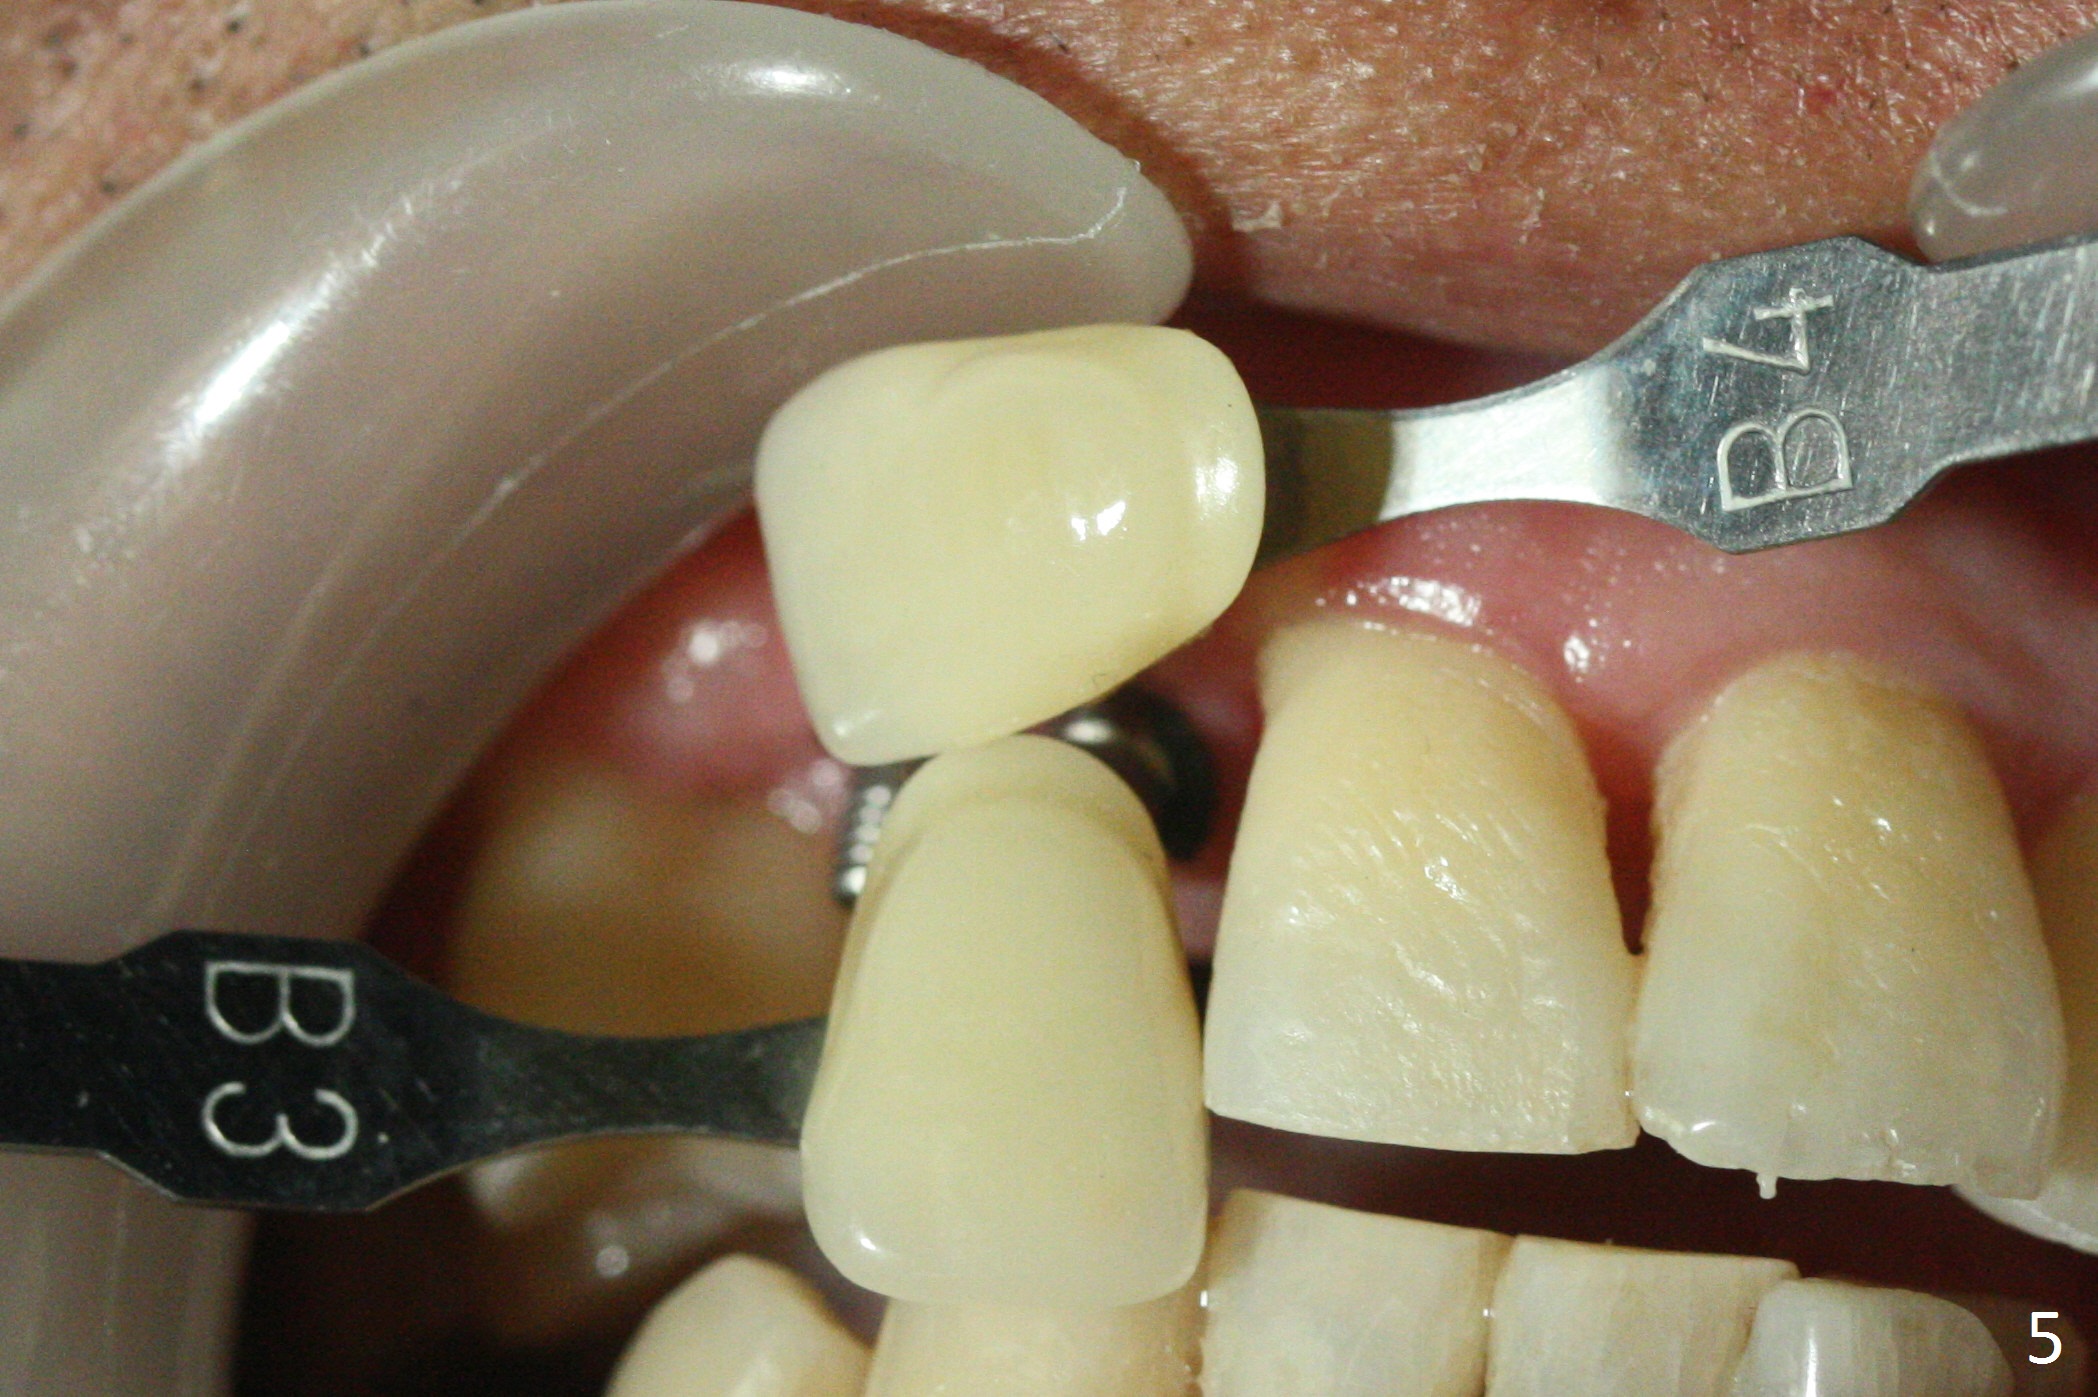

There is no bone loss 3 months postop (Fig.3). After reprep (Fig.4), shades are selected for the final crowns (Fig.5). Before crown cementation at #6 and 7, the patient notes asymmetry with the teeth on the other side (Fig.6). Our concerns are the lack of the papilla distal to #6 (Fig.7 * (multiple modification of provisional needed)) and slight inflammation due to insufficient oral hygiene (^).